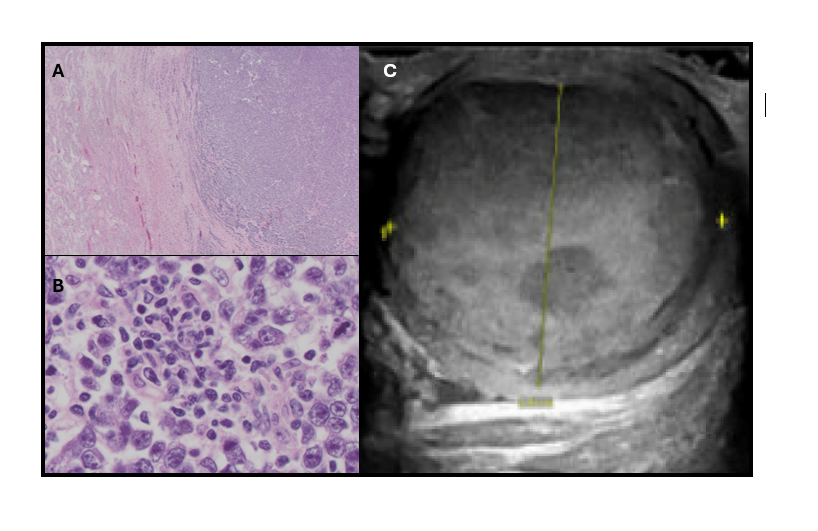

Case Presentation: 26-year-old man diagnosed with T-cell acute lymphoblastic leukemia (T-ALL) with CNS involvement in July 2022 completed one cycle of hyperCVAD B and subsequently received maintenance therapy with POMP (prednisone, vincristine, methotrexate, and mercaptopurine) starting in 2023, along with intrathecal chemotherapy. The patient achieved complete remission, with serial MRIs, PET scans, and bone marrow biopsies remaining negative. During an outpatient follow-up in July 2024, the patient denied new testicular symptoms. However, 1 month later, he reported right testicular firmness, swelling, pain, and back pain, prompting hospital admission. Initial concerns were for focal leukemic infiltrate. A testicular ultrasound revealed a new 4-cm hypervascular mass in the right testis. Serum tumor markers showed low to normal values with, AFP 3.7 ng/ml, LDH 192 U/L, and HCG 1 mIU/mL. Lumbar puncture and bone marrow biopsy results were unremarkable. PET scan revealed testicular uptake. The patient underwent orchiectomy, with pathology confirming a T1b seminoma with negative surgical margins. He will continue active surveillance for testicular cancer, including monitoring serum tumor markers and imaging, as well as complete maintenance therapy for T-ALL.

Discussion: The differential of a testicular mass in this case included recurrent T-ALL versus a primary testis malignancy. T-ALL is rare, given the incidence in the US is 3 cases per million per year. Patients present with cervical, axillary or mediastinal masses (4). “Low” versus “high” risk categories exist depending on certain mutations (7). CNS involvement is common and usually takes the form of leptomeningeal disease (7). In addition to CNS involvement, the testes are also recognized as a sanctuary site in ALL, with testicular relapses reported during or after treatment in B-ALL and rarely in T-ALL (8). Converse to the rarity of isolated testicular T-ALL relapse, testicular cancer is the most common solid malignancy affecting males from 15 to 35 years of age (3). It most commonly presents with a painless or painful testis mass. The diagnostic evaluation includes testicular ultrasound, tumor markers and radical orchiectomy (8, 9). Negative tumor markers do not rule out the diagnosis. Testicular biopsy is contraindicated due to risk of tumor seeding (9). Testicular cancer is highly curable, particularly early-stage seminoma, associated with > 99% 5-year survival following orchiectomy alone (3). Given high cure rates, effective salvage therapy and long-term toxicities associated with additional therapy, the NCCN generally recommends surveillance for Stage I seminoma without additional adjuvant therapy (5, 6).